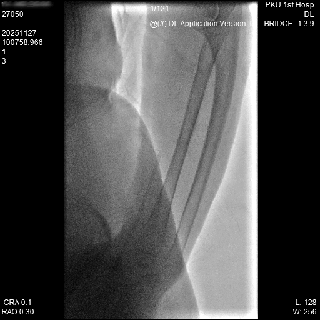

1. 患者仰卧位,左手内旋自然状态置于腹部,左手弯向病人的右腹股沟,左上肢常规消毒铺巾,暴露左手。左侧鼻烟壶处注射2ml利多卡因,使用微穿针以改良的Seldinger法向左侧远桡动脉动脉搏动最强处穿刺,穿刺成功后先置4F短鞘,将猪尾导管选至降主动脉后引入加硬导丝,再交换引入Cordis 6F薄壁长鞘。

动脉长鞘怎么置入桡胜一筹丨杨敏教授团队:应用Brite Tip Radianz长鞘经远桡动脉治疗肾动脉狭窄一例_https://www.jmylbn.com_新闻资讯_第18张

动脉长鞘怎么置入桡胜一筹丨杨敏教授团队:应用Brite Tip Radianz长鞘经远桡动脉治疗肾动脉狭窄一例_https://www.jmylbn.com_新闻资讯_第19张